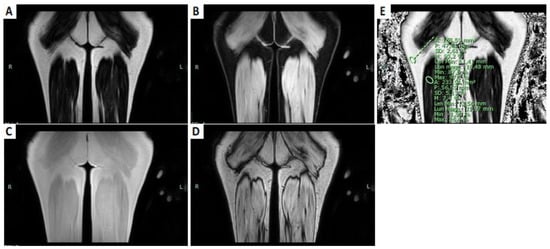

- Fionda, L.; Lauletta, A.; Leonardi, L.; Perez, J.A.; Morino, S.; Merlonghi, G.; Alfieri, G.; Costanzo, R.; Tufano, L.; Vanoli, F.; et al. Muscle MRI in immune-mediated necrotizing myopathy (IMNM): Implications for clinical management and treatment strategies. J. Neurol. 2023, 270, 960–974. [Google Scholar] [CrossRef]